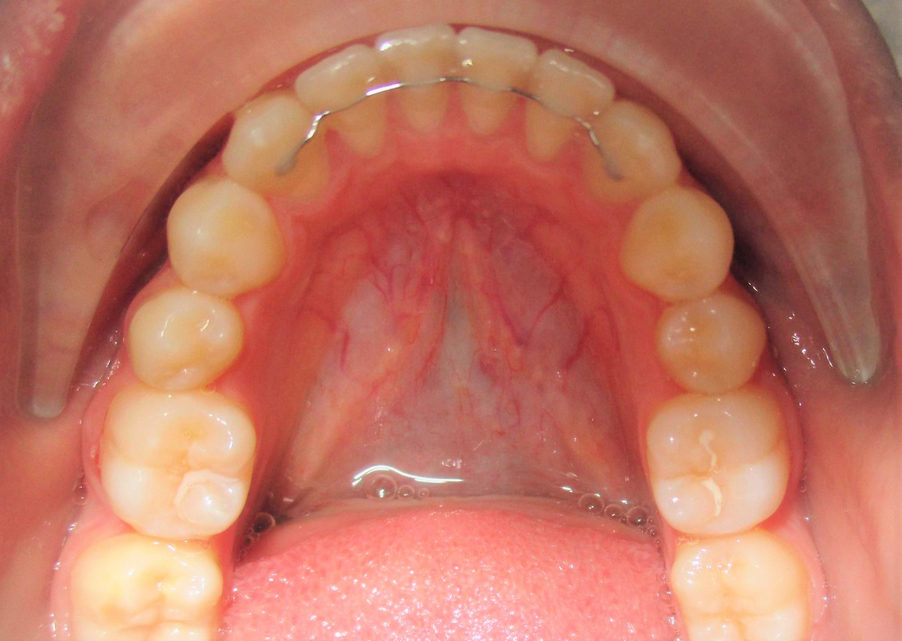

permanent retainer

It is impossible to overstate this, but retainers are the best way to prevent teeth shifting! Retainers come in different designs and forms but the one thing in common is that they should be worn for life! Unrealistic and annoying? may be, but it’s a small price to pay to maintain a beautiful smile for life!